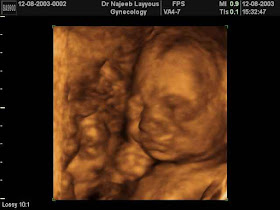

منذ المرحلة المبكرة من الحمل، ينمو الأجنة بمعدلات مختلفة، لذا فإن هذه الأرقام ما هي إلا مجرد معدلات. قد يختلف طول ووزن طفلك كثيراً عن هذه الأرقام. لا تقلقي كثيراً إذا أظهر التصوير بالموجات ما فوق الصوتية أن طفلك أصغر أو أكبر. سوف تعلمك طبيبتك متى يجب القلق بشأن حجم طفلك

مع اكتمال فترة الحمل، قد يزن طفلك أقل من 2.27 غرام أو أكثر من 4.08 غرامات. في الجدول التالي، تمّ قياس الاطفال من أعلى الرأس وحتى المؤخرة حتى بلغوا 20 أسبوعاً من الحمل

بعد الأسبوع 20 من الحمل، تمّ قياس الاطفال من أعلى الرأس حتى أخمص القدمين. وذلك لأن ساقي الطفل تكونان منطويتين باتجاه جذع جسمه في النصف الأول من الحمل مما يصعب كثيراً عملية قياسه. إذا كان لديك أسئلة حول التواريخ، اقرئي مقالتنا كيف يحتسب "بيبي سنتر آرابيا" مرحلة حملك

منذ الأسبوع الثامن وحتى قرابة الأسبوع 20، سيتمّ قياس طفلك من أعلى رأسه حتى مؤخرته كما هو مشار أدناه

وبعد الأسبوع 20، سيتمّ قياس طفلك من رأسه حتى أخمص قدميه